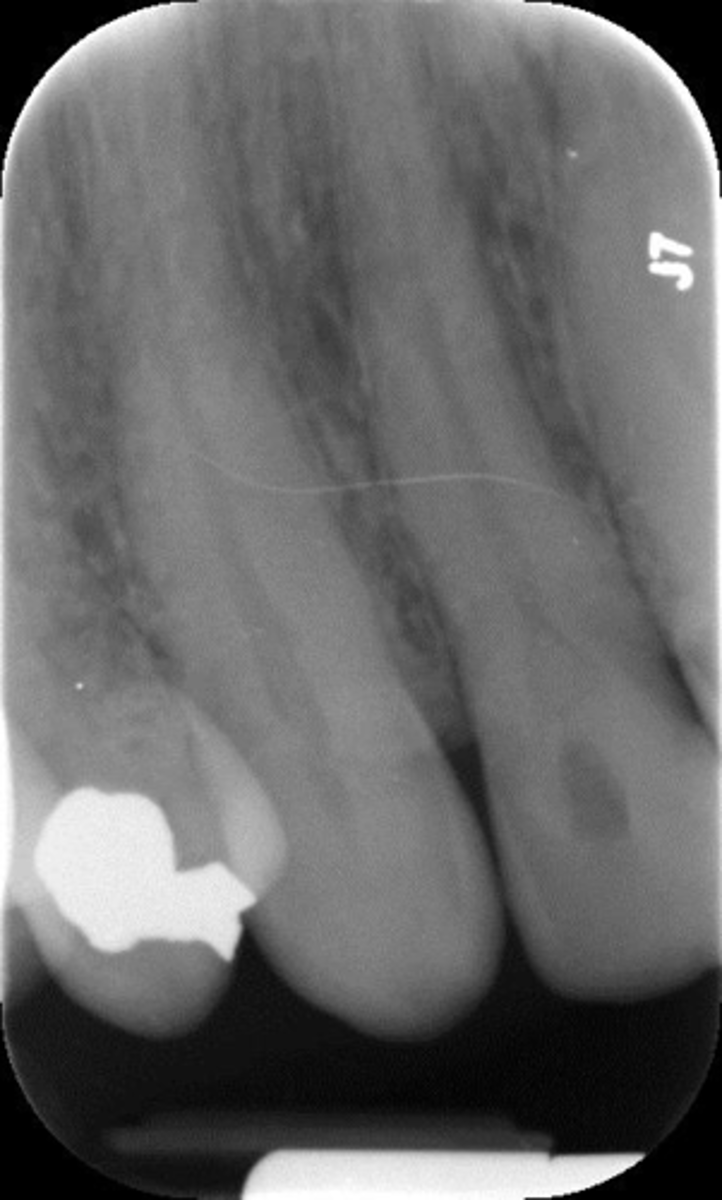

What is this error?

Rinn instrument bar, vertical angulation